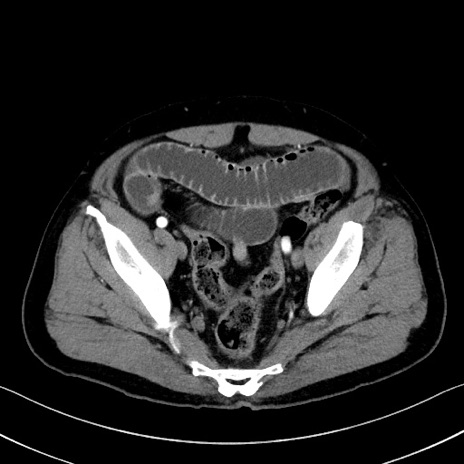

症例35(横断像)

【症例】70歳代 男性

【主訴】腹部膨満、嘔吐

【現病歴】昨日より腹部膨満感出現。本日増悪し、仙痛出現。嘔吐あり、受診。

【既往歴】糖尿病、胆摘後

【身体所見】BP 149/80mmHg、HR 74/min、BT 35.9℃、腹部:膨満、軟、圧痛なし。腸雑音減弱あり。上腹部正中切開瘢痕あり。

【データ】WBC 13500、CRP 1.72